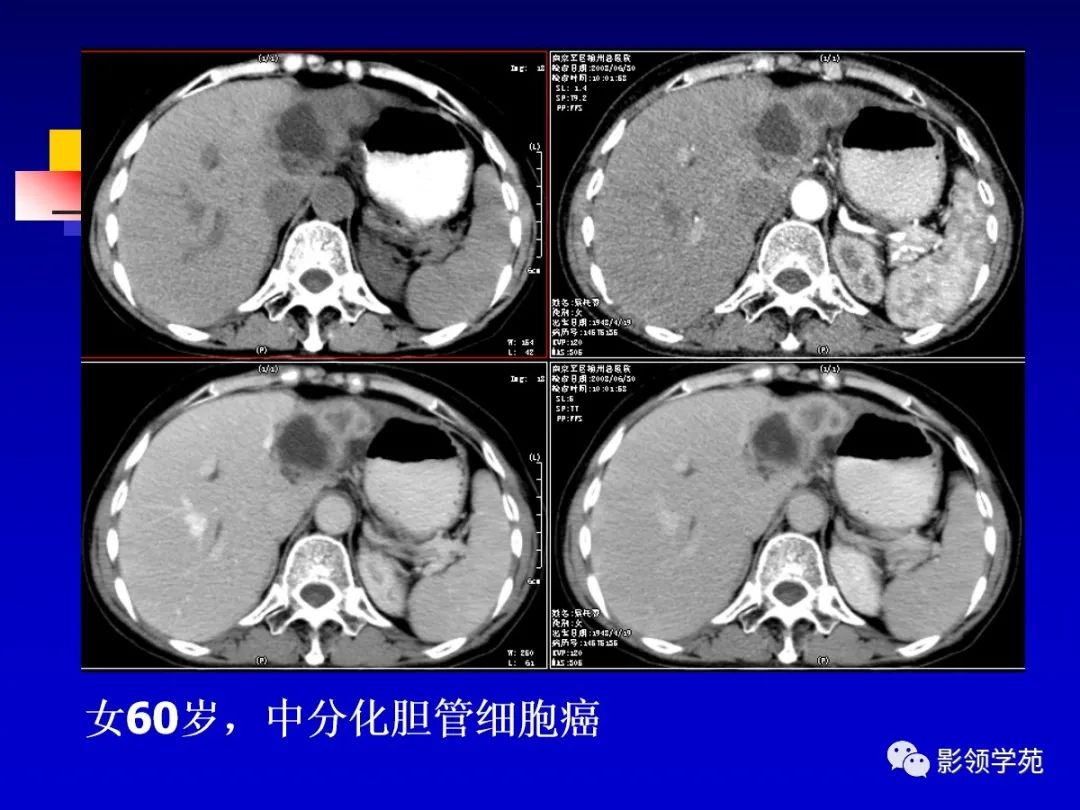

肝细胞肝癌(HCC)与胆管细胞癌(ICC)影像诊断要点